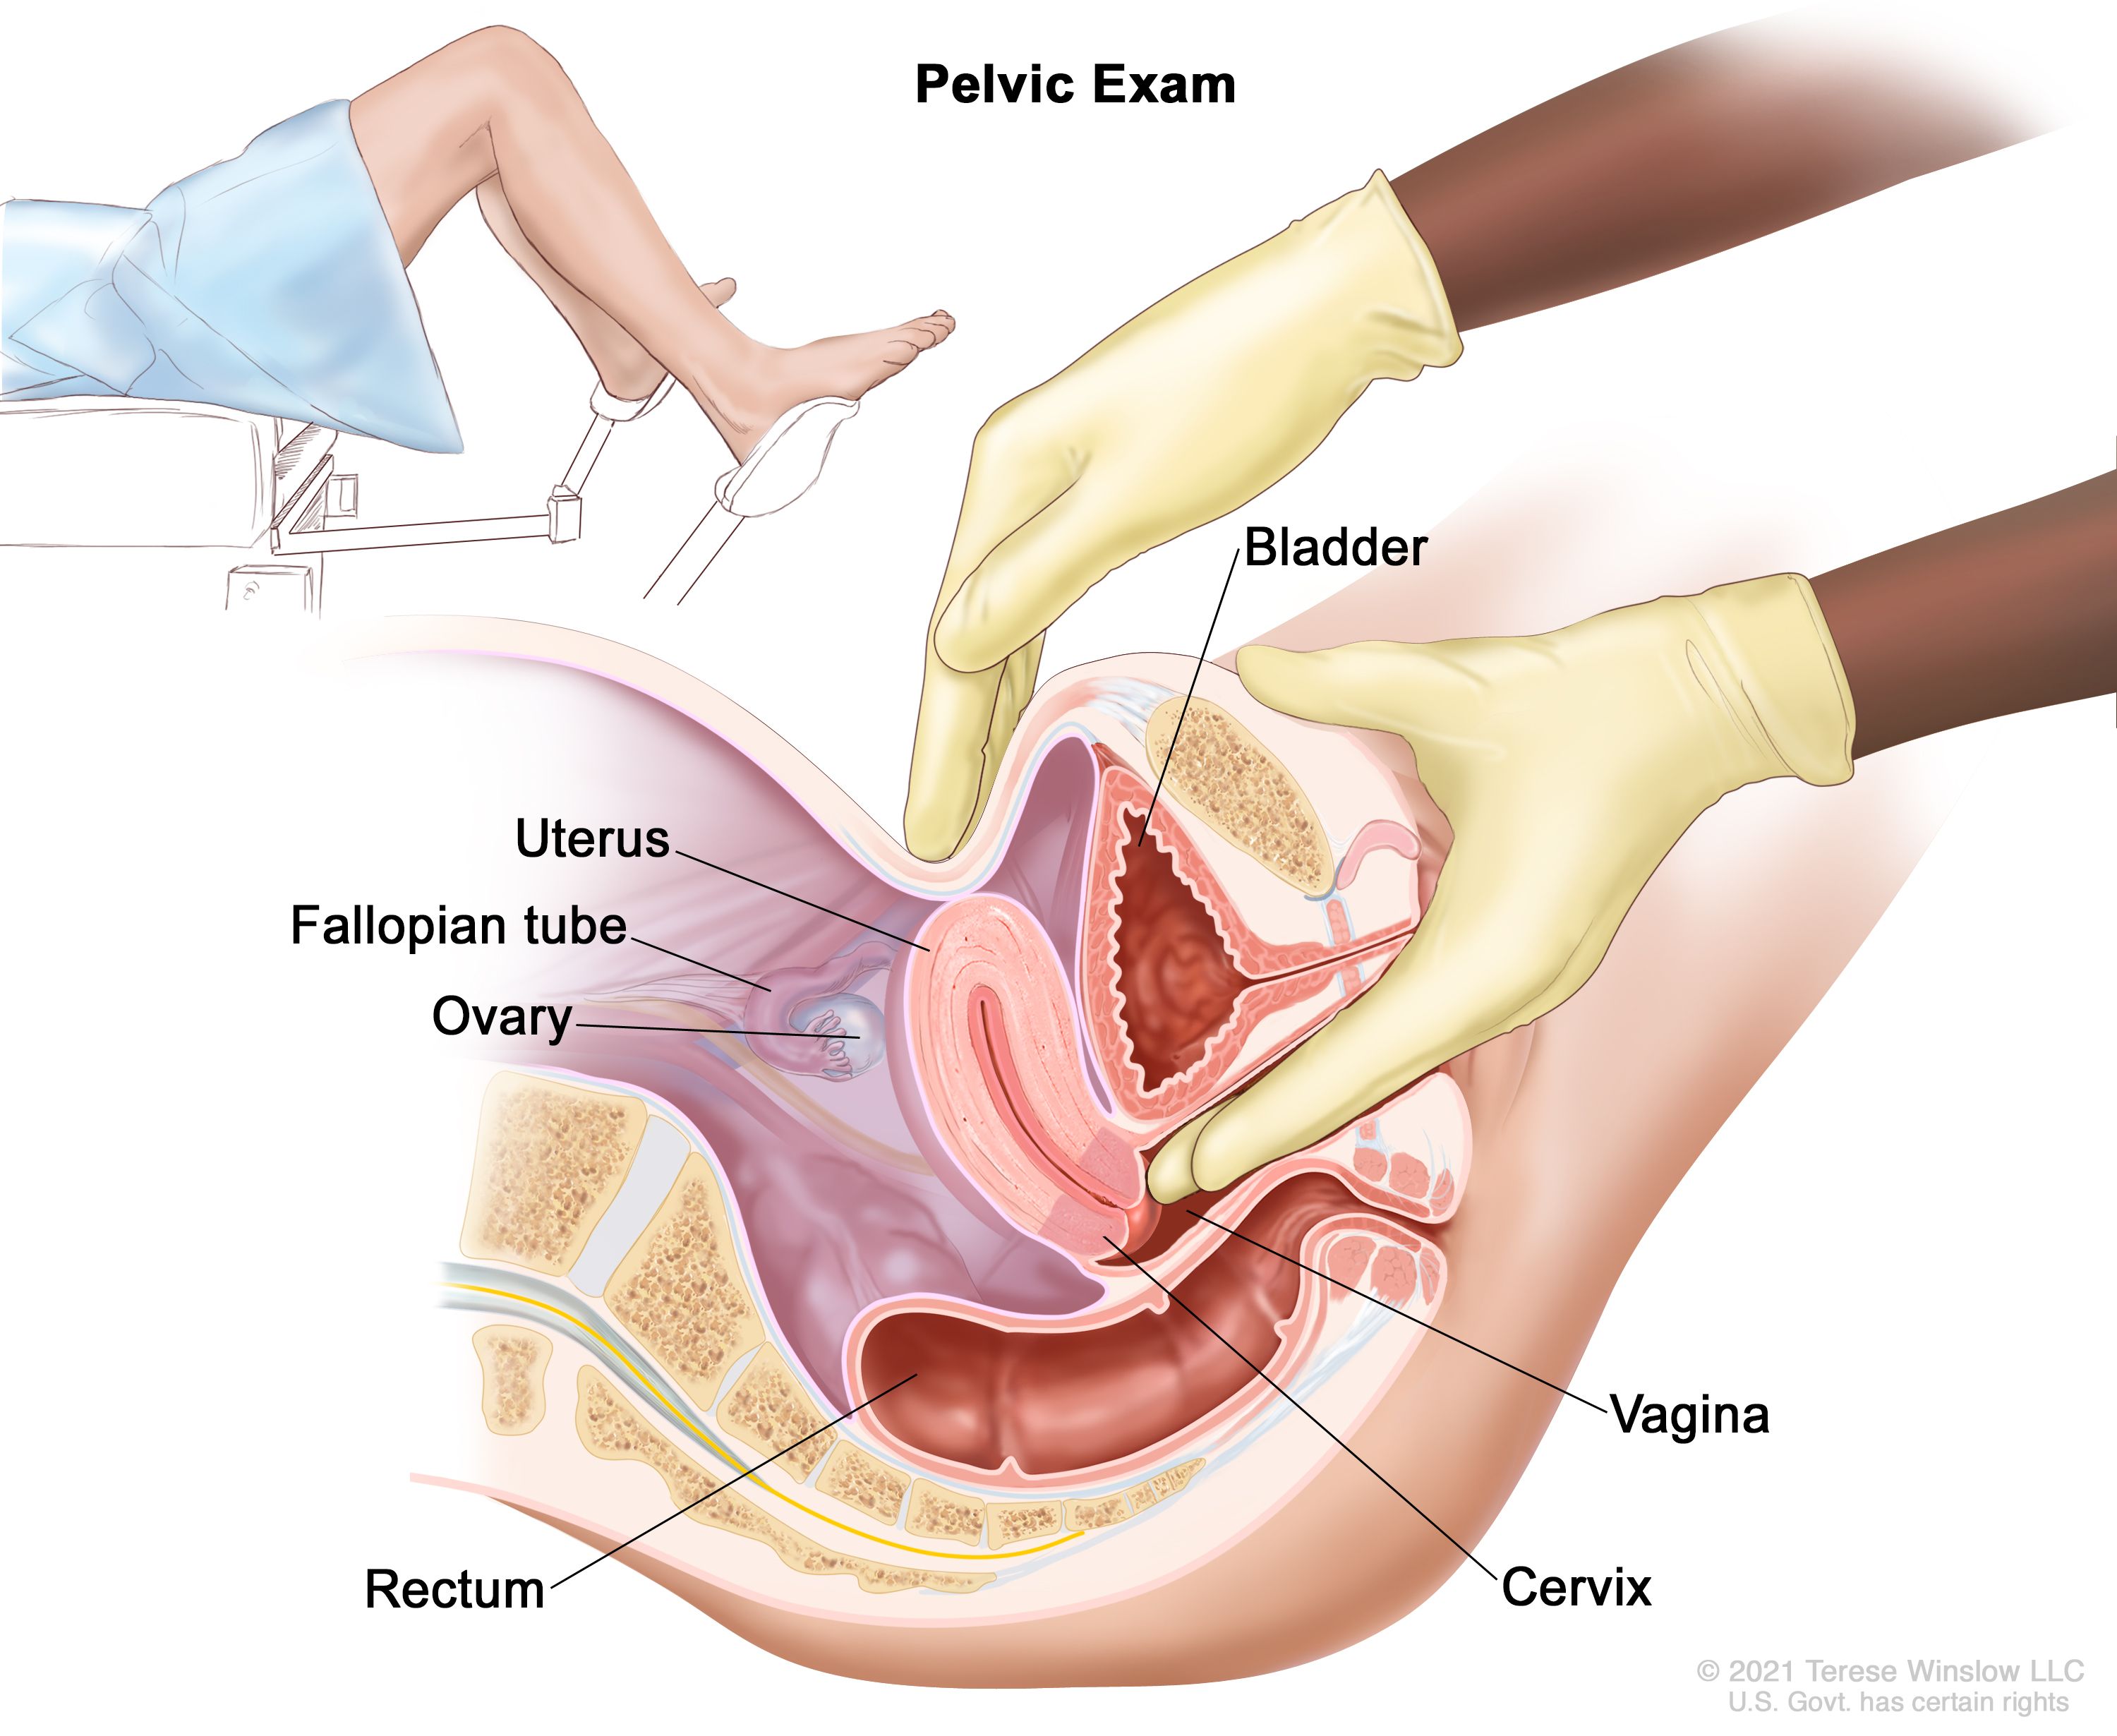

A diet high in fruits and vegetables has been found to be protective against cervical cancer and dysplasia. While it’s not clear if smoking can affect cervical cancer growth or recurrence, it is still helpful to stop. Cervical cancer can be cured if diagnosed at an early stage and treated promptly.

You may strengthen the body's immune system and quite simply create resistance to an hpv infection in basically just a few months, prior to the time that it could originate any important. Ad all cervical cancer treatments are not the same is what you've tried not working? Learn about the stages of cervical cancer and what they mean.